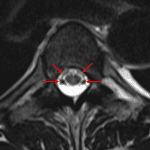

- Central cord T2/STIR hyperintensity from the levels of T5-T10 with associated mild cord expansion and possible mild enhancement

- Prominent intrathecal vessels at the level of T9-T10

- Spinal dural arteriovenous fistula

Central cord edema spanning T5-T10 with associated mild cord expansion and possible mild enhancement, which in combination with the finding of serpiginous vessels in the thecal sac at the level of T9-T10 raises concern for a dural AV fistula. Additional diagnostic considerations include cord infarct and transverse myelitis. Recommend neurosurgical evaluation and consideration of catheter angiography.